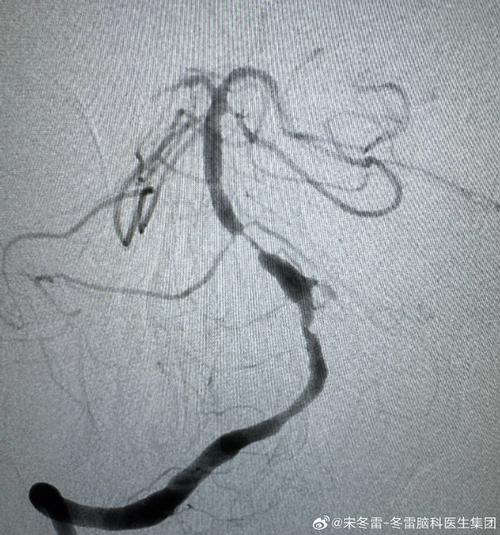

(图片来源网络,侵删)